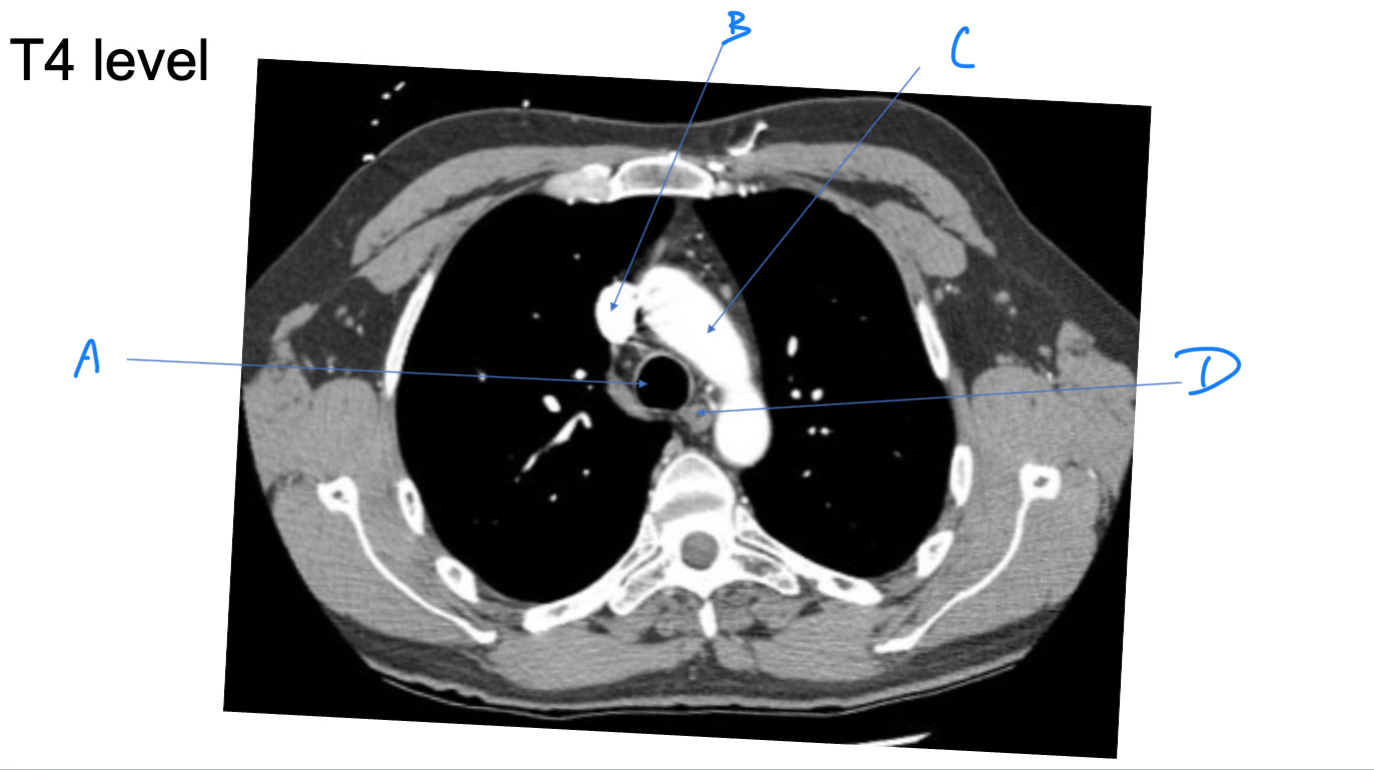

Esophagus

A. Identify

Trachea

B. Identify

R Brachiocephalic v.

C. Identify

Brachiocephalic trunk

D. Identify

L CCA

E. Identify

L Brachiocephalic v.

F. Identify

L Subclavian a.

G. Identify

Trachea

A. Identify

Superior vena cava (SVC)

B. Identify

Arch of aorta

C. Identify

Esophagus

D. Identify